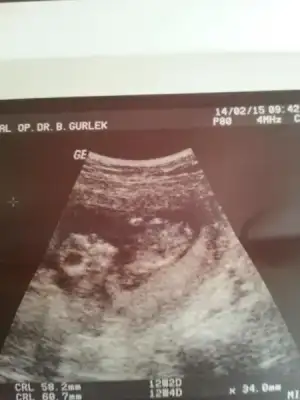

Farklı bir ultrason koymuştum ama fatoş arkadaşta ikiliem de kalmıştı, cinsiyet namında tahmin zordu biraz, hem kıza hem erkeğe benziyor demişti bu resim daha net, doktor da %85 kız demişti bu arada.. :emir_bebek::16:

Ha unutmadan bebek benim değil, arkadaşımın buna dair bir belirtme yapmadığımı yeni farkettim. :9: